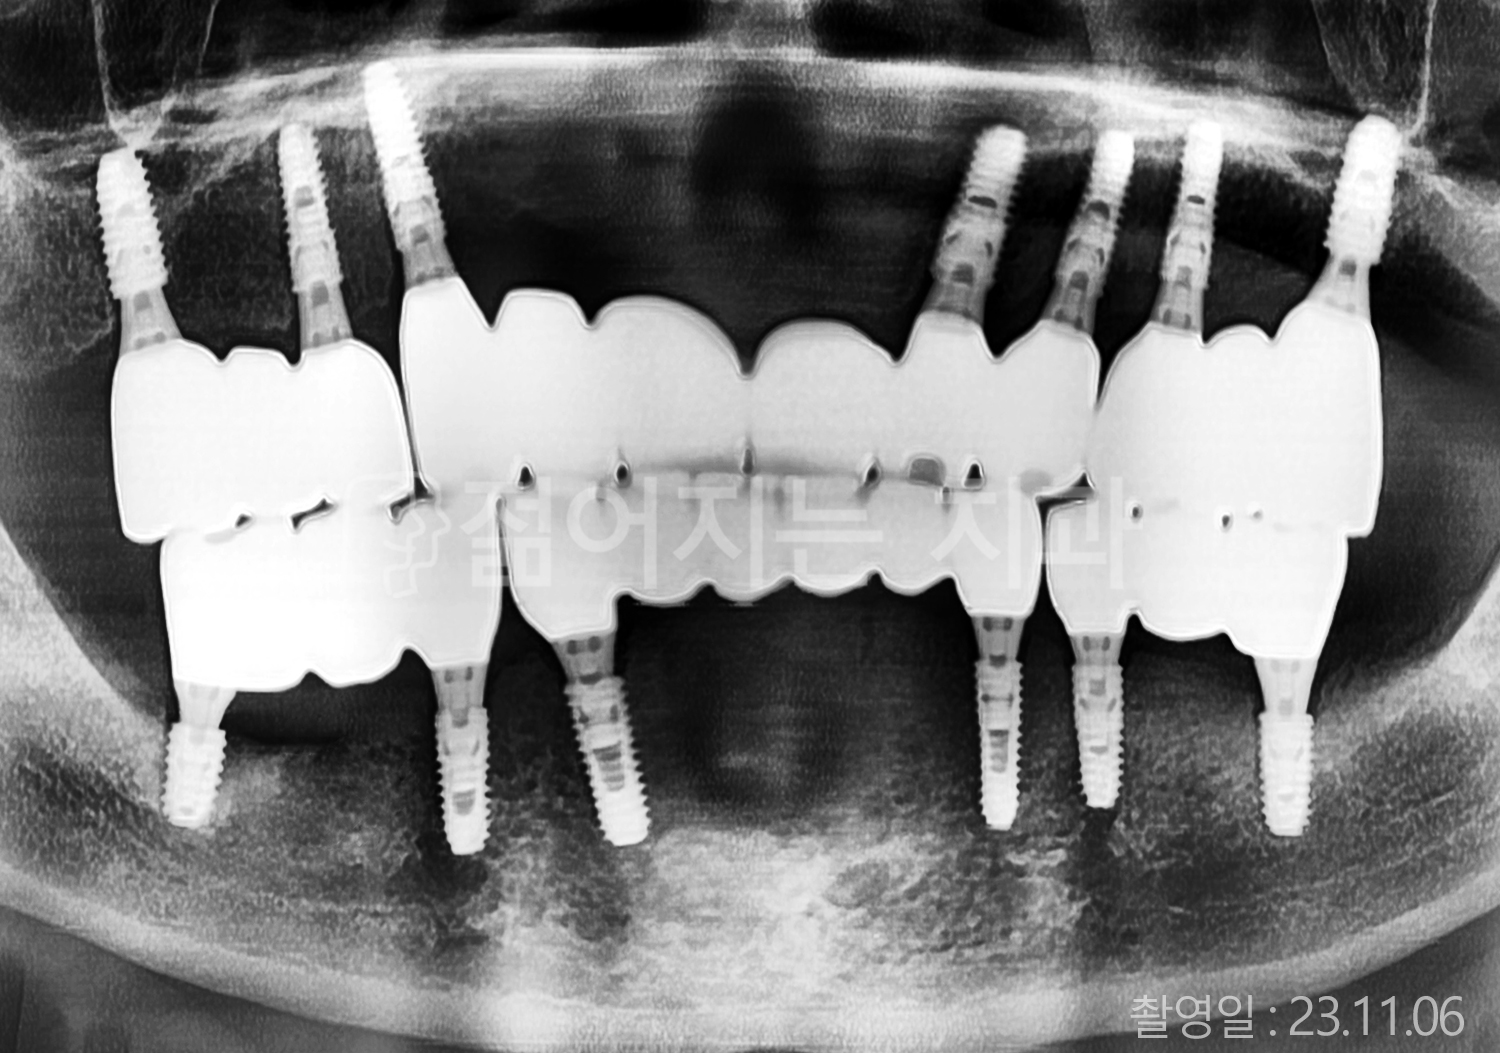

• 40대 전체치아 10개 이상 임플란트

• 70대 당뇨 전체치아 10개 이상 임플란트

• 60대 전체치아 10개 이상 임플란트

• 60대 고혈압, 당뇨, 고지혈증 전체치아 10개 이상 임플란트

• 50대 전체치아 10개 이상 임플란트

• 70대 고혈압, 당뇨 전체치아 10개 이상 임플란트

• 60대 고혈압 전체치아 10개 이상 임플란트

• 50대 고혈압, 당뇨, 고지혈증 전체치아 10개 이상 임플란트

• 60대 고혈압, 고지혈증 전체치아 10개 이상 임플란트